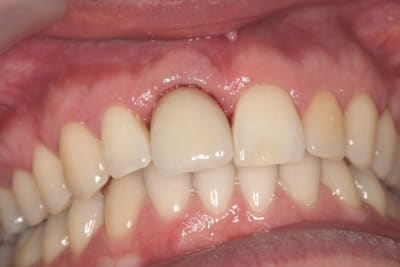

le hasard fait parfois bien les choses...patient revu ce matin pour une "bricole" sur une restauration postérieure...

il est intéressant de voir la maturation des tissus mous...et en plus VS des différences au niveau de l'hygiène, pas mal secteur 2 mais perfectible secteur 1...

ici on est à 3 mois post pose prothèses d'usage...la photo, prise un peu décalée, donne l'impression d'une différence de hauteur des collets, mais il n'en est rien (ou alors très peu...)

quand même content du résultat...;-) même si j'ai (lourdement)insisté pour que l'hygiène soit un peu mieux suivie...